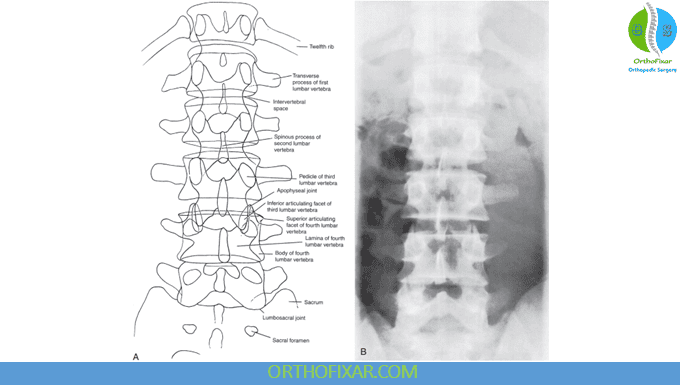

Anteroposterior (AP) View

In the AP lumbar vertebrae X-ray, the examiner should assess:

- Shape of the vertebrae — look for any wedging or compression suggesting a fracture.

- Intervertebral disc spaces — assess for reduced height as seen in spondylosis.

- Vertebral deformities — such as hemivertebrae or other congenital anomalies.

- Bamboo spine — characteristic of ankylosing spondylitis.

- Transitional vertebrae:

- Lumbarization of S1 (seen in 2–8% of the population), where S1 behaves like a lumbar vertebra, making S1–S2 the first mobile segment.

- Sacralization of L5 (3–6% incidence), where L5 fuses with the sacrum, making L4–L5 the first mobile level.

- Spina bifida occulta, which may be seen in 6–10% of individuals.